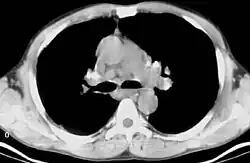

Sarkoidoza, choroba Besniera-Boecka-Schaumanna (łac. sarcoidosis) – choroba układu odpornościowego charakteryzująca się powstawaniem ziarniniaków (małych grudek zapalnych), które nie podlegają martwicy. Praktycznie każdy organ może być nią dotknięty, chociaż najczęściej pojawia się w węzłach chłonnych i płucach. Objawy mogą się pojawić nagle, ale najczęściej postępują stopniowo. W obrazie rentgenowskim płuc sarkoidoza może przypominać gruźlicę lub chłoniaka.

W obrębie układu oddechowego sarkoidoza najczęściej objawia się jako choroba restrykcyjna płuc powodująca spadek ich objętości oraz podatności (zdolności do rozciągania). Pojemność życiowa płuc jest zmniejszona i większa część powietrza może ulec wydmuchnięciu w ciągu pierwszej sekundy (wzrasta FEV1). To oznacza, że stosunek FEV1/FVC również wzrasta.